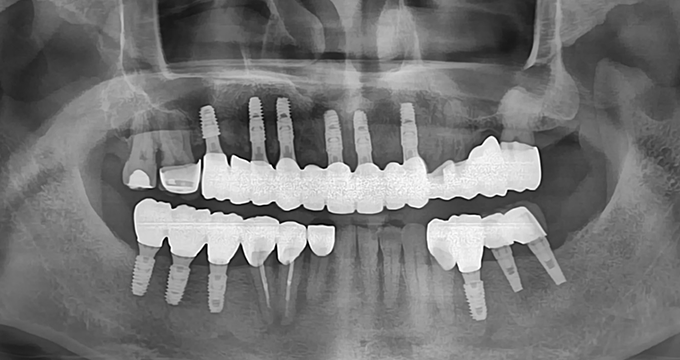

치료 후

40대 남성 환자분으로, 위 아래 치아들이 전체적으로 망가짐에 따라 얼굴의 '수직고경'이라고 하는 하안면의 높이가 줄어들어 있었습니다.

무너졌던 교합고경이 회복되어 치료 전 합죽이처럼 보이던 하안모가 연령에 맞는 정상적인 외형으로 복구되었습니다.